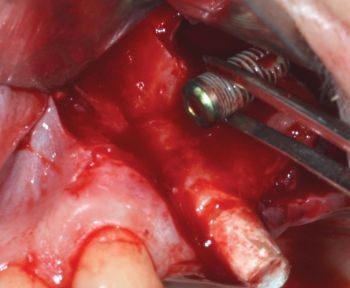

The antrostomy was progressively enlarged in both mesial and cranial directions using an ultrasonic tip to improve intraoperative visibility and facilitate localization of the implant (Figs. 8–10).

When Implants Go Rogue

Fig. 8: Progressive enlargement of the antrostomy in the mesial direction

Fig. 9: Progressive enlargement of the antrostomy in a cranial direction